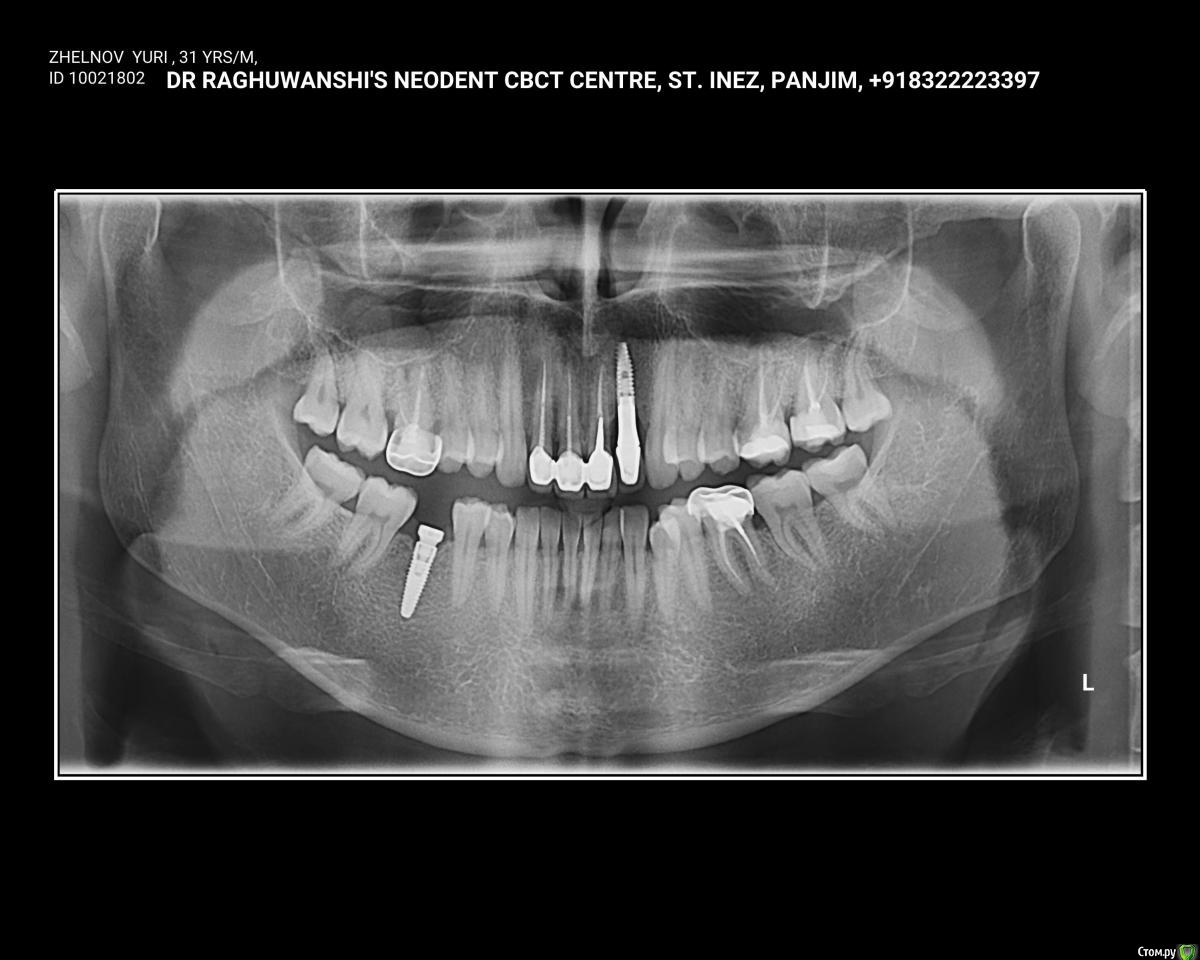

ylzhelnov Опубликовано 10 февраля, 2018 Поделиться Опубликовано 10 февраля, 2018 Здравствуйте. Болит зуб под коронкой (слева снизу). Коронка металл, 11 лет, до этого не беспокоил. Я сейчас в Индии, сделан снимок, жду ответа от местного доктора. Боль купируется ибупрофеном (хватает на 12 часов) или детским гелем при прорезывании зубов "Первые зубки". Посоветуйте, пожалуйста, порядок действий, лечения. Ссылка на комментарий

DmitrySH Опубликовано 10 февраля, 2018 Поделиться Опубликовано 10 февраля, 2018 И подскажите, я планирую менять коронки на 6-м нижнем слева и справа сверху + вкладки в 6-й и 7-й слева сверху. Нужно ли каналы перелечивание где-либо? Лучше всего сделать КТ, будет понятнее. У корней зубов 1.6 и 2.7 точно есть хроническое воспаление. Зубы 2.6 и 3.6 посмотреть на КТ, скорее всего там тоже не все благополучно , и тоже перелечить Ссылка на комментарий